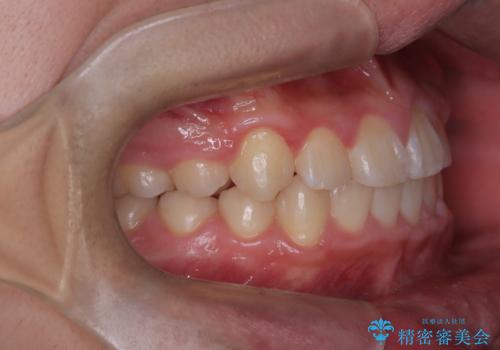

八重歯・歯並びのデコボコとディープバイトを改善した抜歯ワイヤー矯正症例

- 八重歯と咬み合わせを治したいを主訴にご来院された患者様です。

矯正の精密検査の結果上顎左右4番の計2本を抜歯し、審美性に配慮したワイヤー矯正装置(審美装置)を用いて治療を行いました。

八重歯などの歯列のデコボコが綺麗に改善され、患者様にも大変喜んでいただけました。また、咬み合わせが深い「ディープバイト」も併せて改善し、見た目だけでなく機能面でもバランスの取れた咬合を獲得しています。